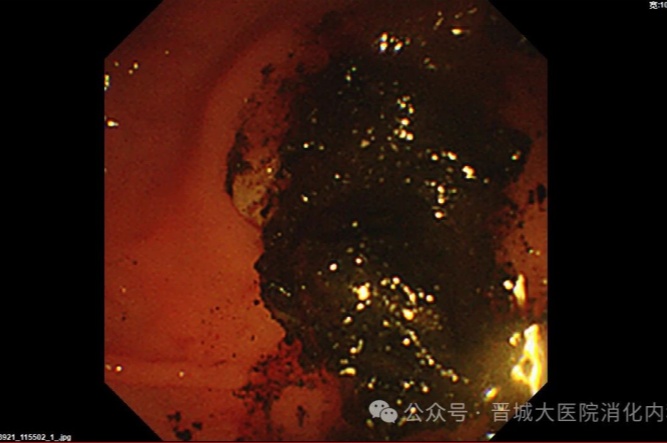

手術(shù)中,普通外科首先為李阿姨行“腹腔鏡膽囊切除”(LC),消化內(nèi)科團隊緊隨其后行ERCP,造影發(fā)現(xiàn)膽總管內(nèi)有多個巨大結(jié)石,最大約2.5×2.1厘米,且結(jié)石堅硬,形如煤渣樣,使用取碎石一體網(wǎng)籃多次反復(fù)碎石、取石。用生理鹽水反復(fù)沖洗膽道,無結(jié)石殘留。利用微創(chuàng)技術(shù)順利完成膽囊切除及膽總管結(jié)石取石,手術(shù)時間短、創(chuàng)傷小、恢復(fù)快。